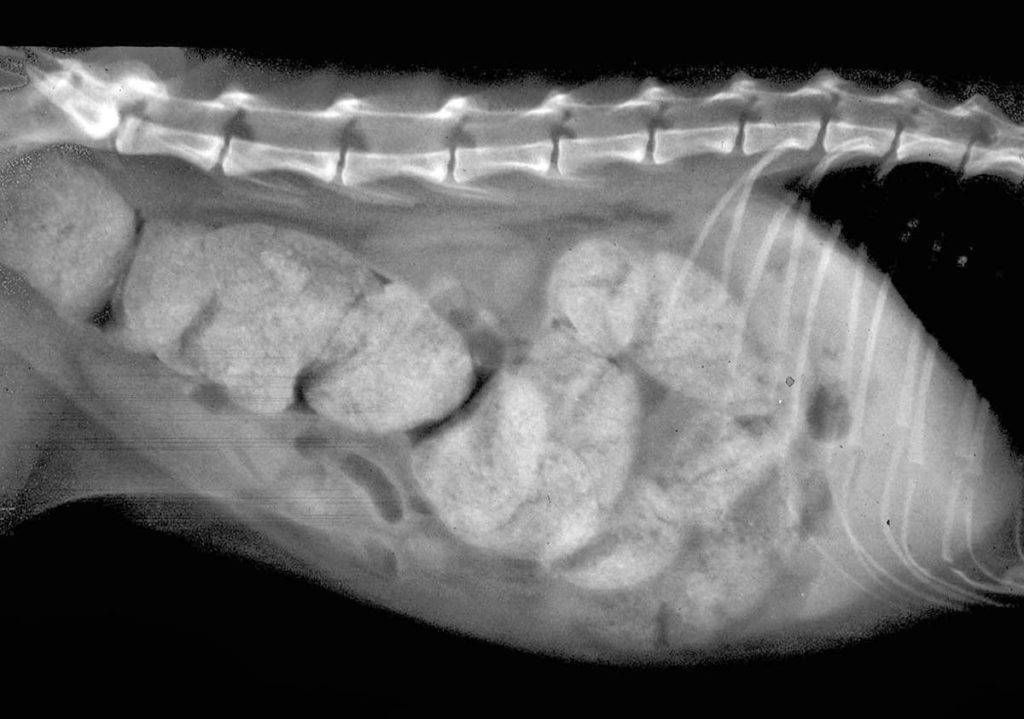

- посторонний предмет в кишечнике (проглоченный инородный объект);

Для малыша двух месяцев от роду рацион расширяется еще сильнее, котятам начинают давать витаминные прикормки. Кроме того, в 2–3 месяца котята ведут очень активную жизнь, много играют. Во время игры или исследования окружающего пространства малыши могут проглотить небольшие предметы, которые закупоривают кишечник или просто затрудняют прохождение кала.